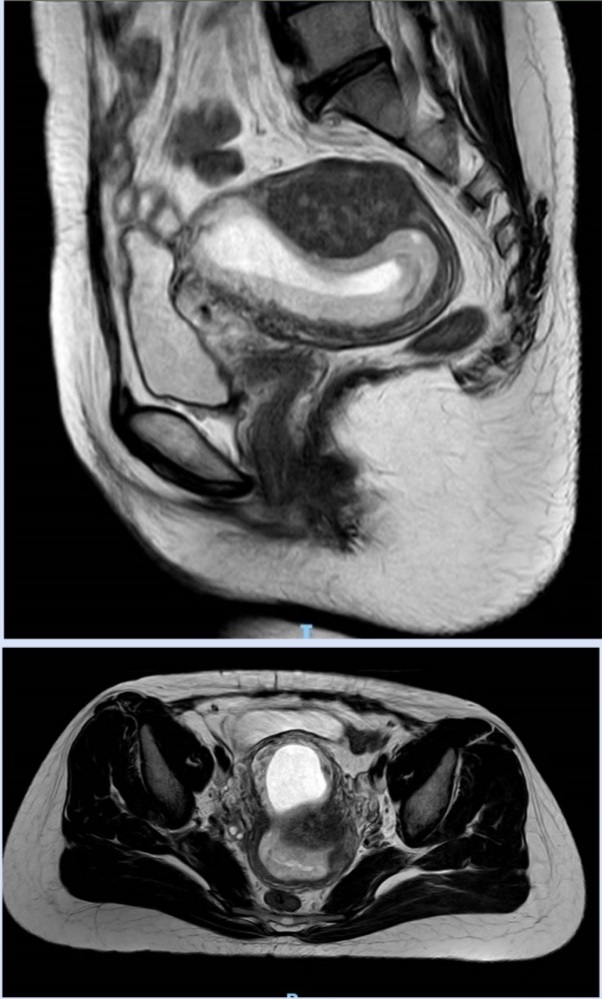

入院后完善相关检查,盆腔核磁如图1所示。

图1

盆腔MRI:子宫后位,体积增大,宫腔见妊娠囊,着床处子宫肌层变薄。下段延伸至宫颈内口,大小约3.4cm*8.4cm。增强扫描妊娠囊及蜕膜强化。妊娠囊部分突向原子宫瘢痕凹陷内,该处肌层菲薄,厚度<3mm,该处子宫轮廓外突,膀胱浆膜完整,瘢痕处见迂曲的血管。考虑子宫瘢痕妊娠(III型)。